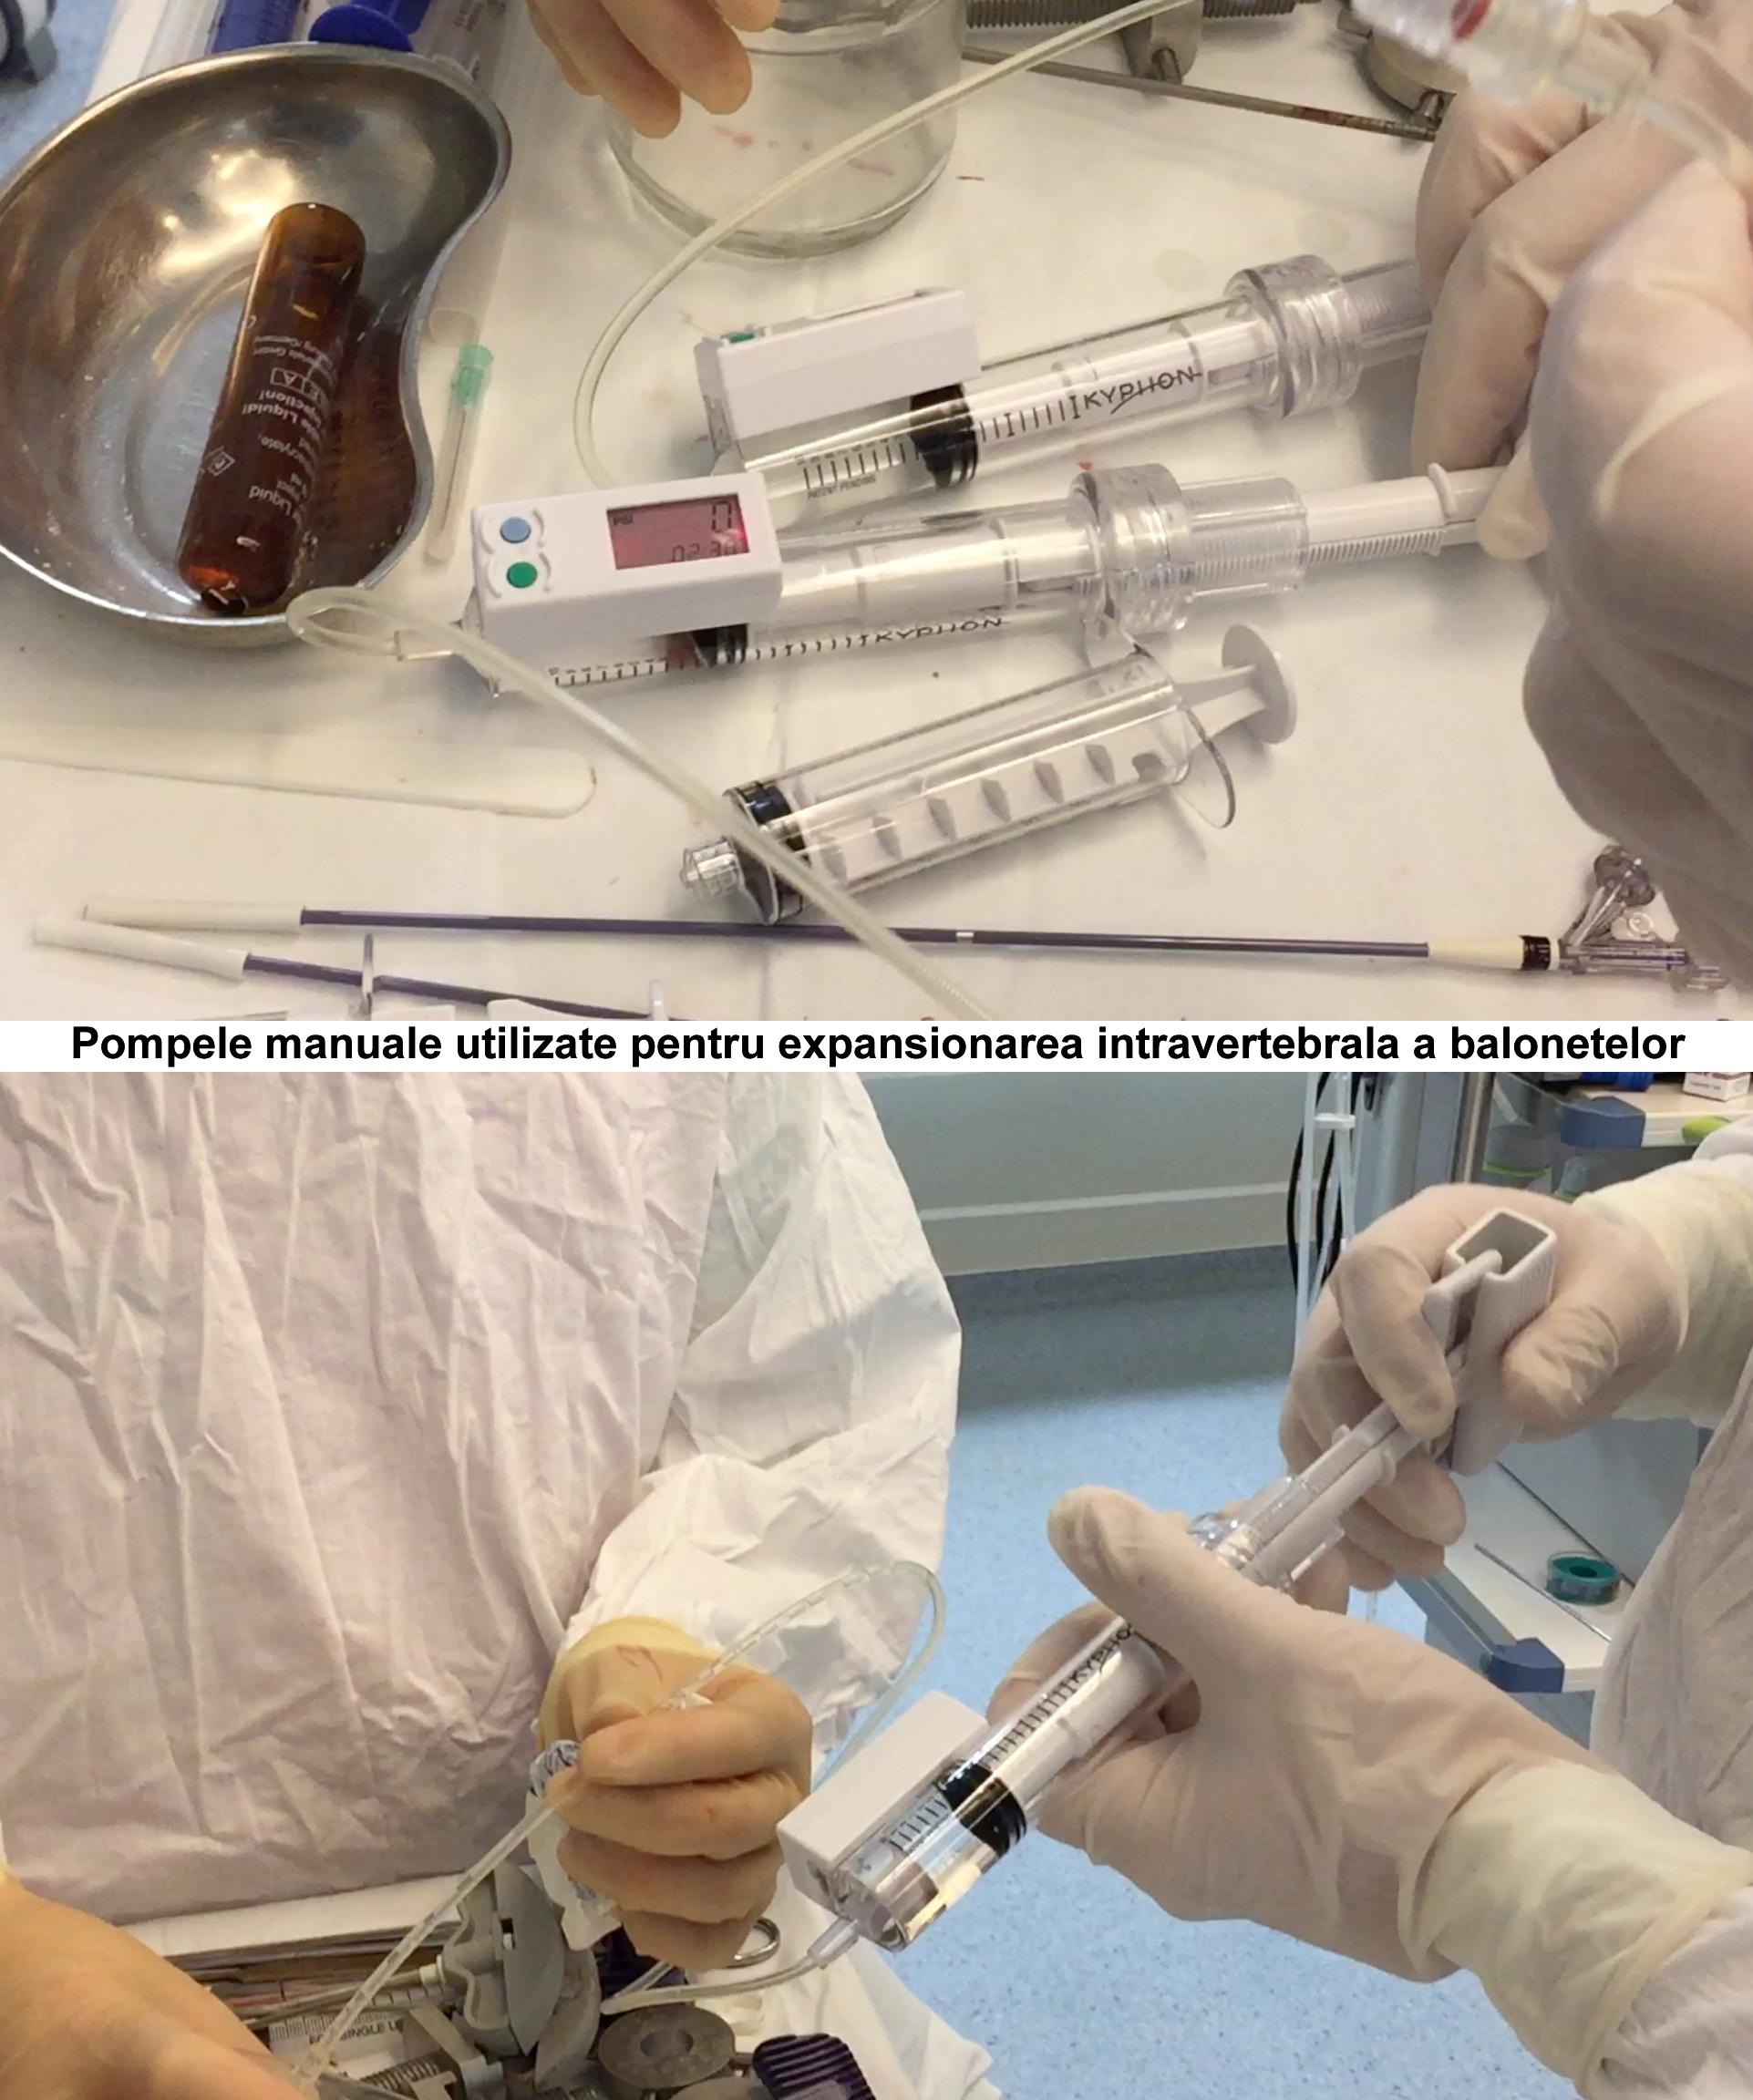

Kyfoplastia reprezintă o procedură minim invazivă în timpul căreia chirurgul introduce în corpul vertebral un tub cu un balon expandabil. Sub control fluoroscopic are loc expansionarea balonului în corpul vertebral, cu restabilirea înălţimii corpului vertebral şi corijarea diformităţii kifotice. Ulterior, în cavitatea formată de balon, se introduce cimentul acrilic, ceea ce contribuie la consolidarea vertebrei.

Realizarea intervenţiilor percutanate de acest tip presupune utilizarea unui fluoroscop intraoperatoriu, cu scopul de a reduce la minim complicaţiile (cum ar fi, leziuni ale structurilor nervoase, scurgerea cimentului extracorporeal, embolii venoase, etc.). În cazul pacientei noastre, a fost utilizată instalaţia de Angiografie tridimensională (3D) Siemens ”Artis Zee”, disponibil în sala de operaţii Hybrid a Spitalului Clinic Republican, care asigură o calitate excepţională a imaginilor intraoperatorii.

Operaţia a fost realizată de Alexandru Şumleanschi, medic neurochirurg, asistat de, profesorul universitar Aurel Bodiu, şeful secţiei Neurochirurgie SCR. Intervenţia a decurs fără complicaţii şi incidente intraoperatorii. În cadrul intervenţiei chirurgicale a fost introdus cimentul acrilic în ambele vertebre lombare, iar structurile nervoase şi vasele magistrale nu au avut de suferit. Pacienta a fost mobilizată la a doua zi postoperator şi externată în stare satisfăcătoare la doar trei zile după intervenţie.